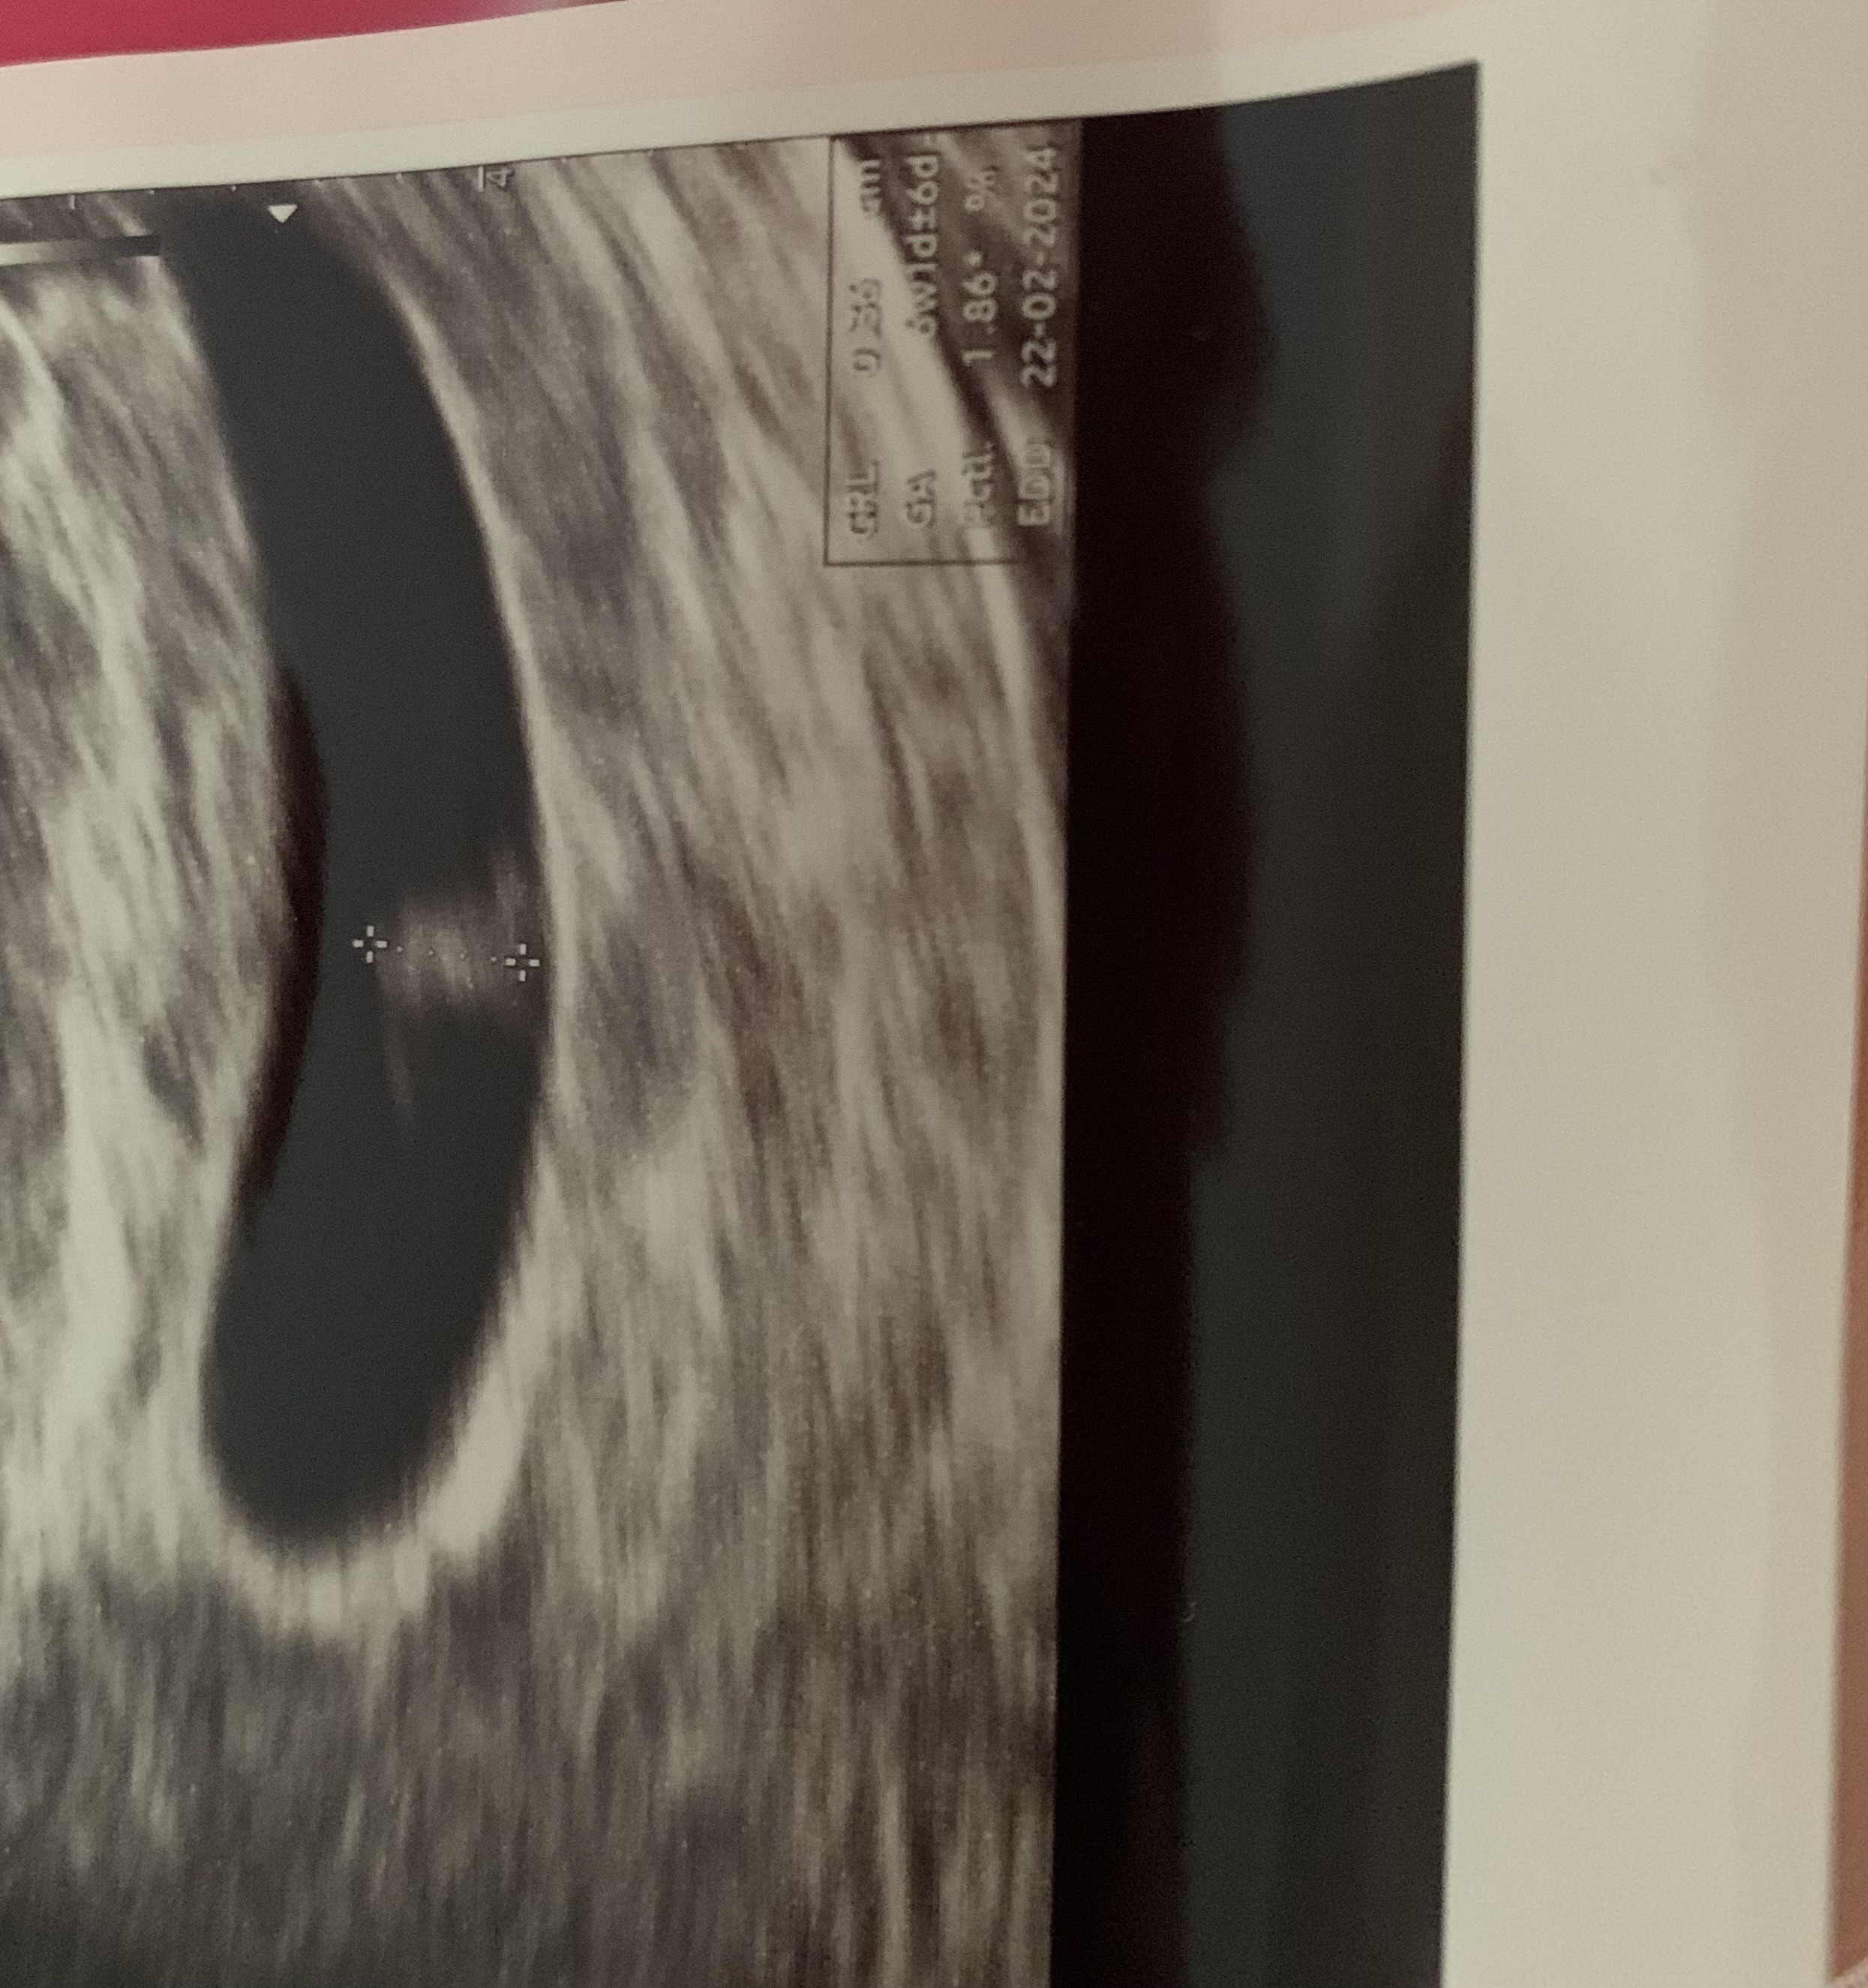

Mam jeszcze jedno spostrzeżenie co do mojej ciąży i jej wieku😊 na Usg z 30 czerwca doktor po Usg stwierdził 6tydzien1 dzień. Zdjęcie wysyłam poniżej. Na którym mam pomiar CRL 0.36cm czyli odpowiedni dla tego tygodnia. Z miesiączki wychodziłby 7 tydzień 5 dzien.

• IMG_4660.jpeg

IMG_4660.jpeg

1,2 MB · Wyświetleń: 61